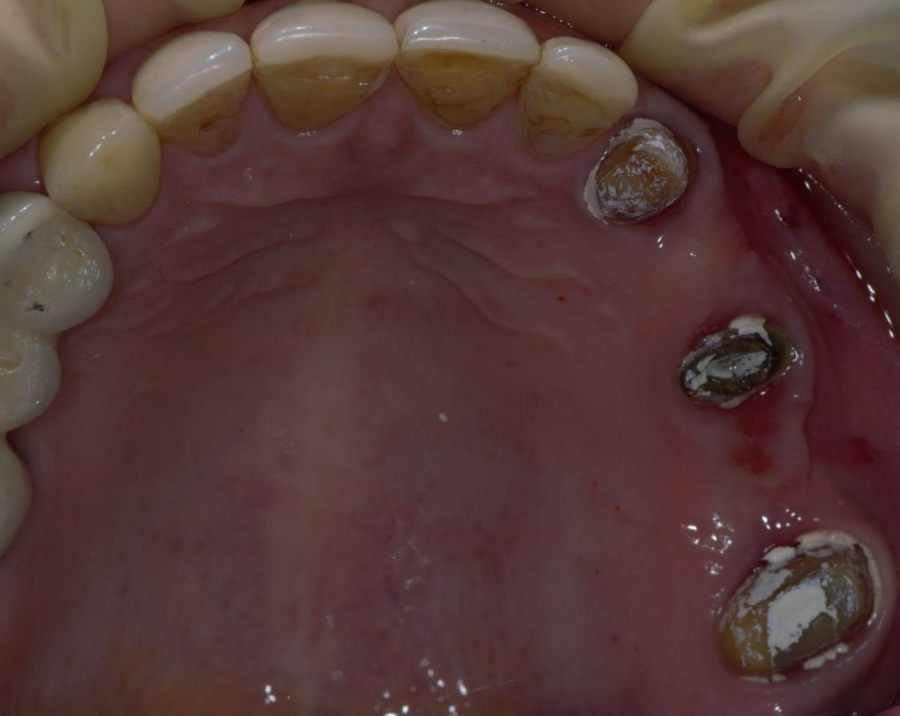

The old PFM bridge was removed, followed by the extraction of the root remnants of tooth 15.

Three Straumann BL® implants with a standard conical connection were placed in positions 14, 15, and 16. Notably, a short implant was selected for position 16 to avoid penetrating the maxillary sinus and perforating the Schneiderian membrane (see radiograph below).

Teeth 13 and 17 remained vital; therefore, crowns were fabricated for these prepared teeth.